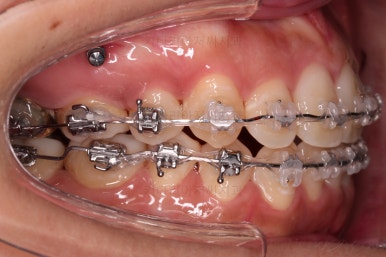

밀고 당기기를 위해서 미니스크류를 셋팅했고요.

교합과 중앙선 및 디테일을 맞춰 나갑니다.

부산재교정 이니만큼 원하는 부분을 최대한 수용하여 개선하고 마무리를 합니다.